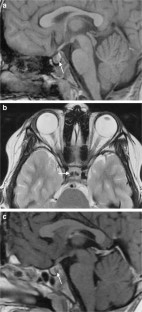

Fig. 1